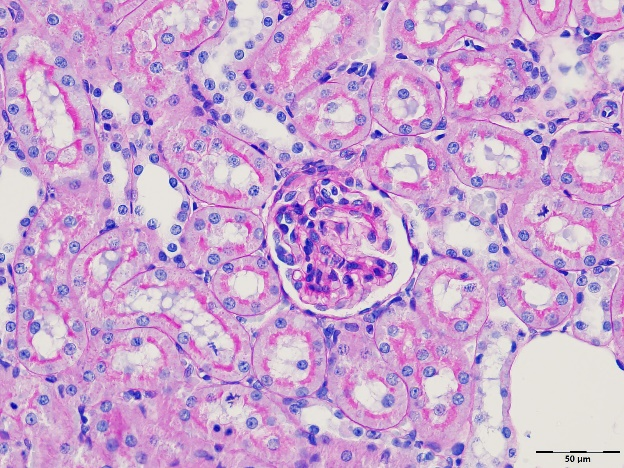

本平台提供覆盖广泛的病理检测服务,包括常规染色(HE染色、特殊染色)、免疫组化(IHC)及免疫荧光(IF)等技术手段。服务适用于动物及人源组织样本,帮助科研人员深入评估组织形态、细胞标志物表达及病理状态,广泛用于机制研究、药效验证及临床前评价。我们依托标准化流程与丰富经验,为客户提供高质量、可重复的组织学研究数据支持。

图像质量高:成像清晰,适用于SCI论文、项目申报、专利材料